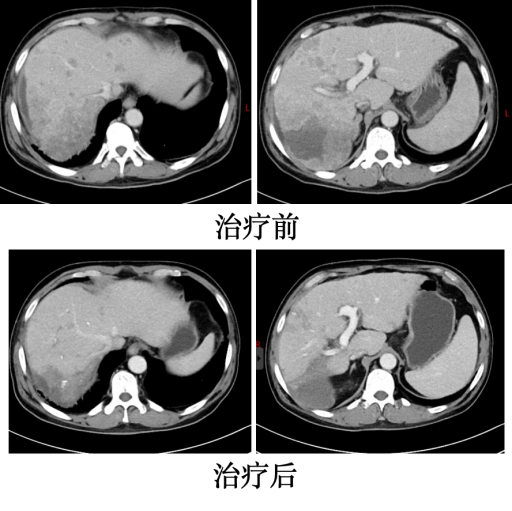

出院后,医生嘱咐患者在当地医院定期接受靶向免疫治疗,并复查血常规、肝肾功能等指标。同时,朝阳医院肝胆胰脾外科的医护人员也定期随访,随时答复患者的相关咨询。近期,患者再次来到朝阳医院复查。结果显示:患者一般情况明显好转,肿瘤标记物全部正常。腹部增强CT检查提示:右肝巨大肿瘤已缩小至6.5厘米,且增强后病灶无明显强化,肝内转移灶和腹腔转移淋巴结明显减少。这表明肿瘤得到了明显控制。